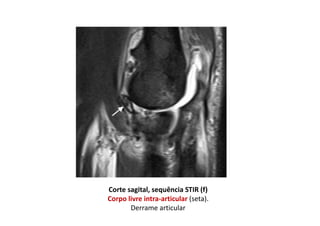

Ressonância magnética do cotovelo direito

Corte coronal, sequência T1 (a)

(a) Osteófitos marginais no côndilo umeral medial e na ulna (setas), irregularidade dos

contornos do osso subcondral do úmero, rádio e ulna

Cortes coronais (anterior para posterior), sequência STIR (b, c)

(b) Indefinição da porção proximal do ligamento colateral radial (seta preta).

Fratura da margem medial da cabeça do rádio, com extensão articular (seta branca).

c) Espessamento heterogêneo e ondulação do tendão comum dos extensores (seta).

Significativo edema dos planos gordurosos da região lateral do cotovelo.

Edema intra-muscular peri-articular

Corte sagital, sequência STIR (f)

Corpo livre intra-articular (seta).

Derrame articular